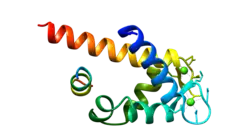

Annexin A1, also known as lipocortin I, is a protein that is encoded by the ANXA1 gene in humans.[5]

Annexin A1 belongs to the annexin family of Ca2+-dependent phospholipid-binding proteins that have a molecular weight of approximately 35,000 to 40,000 Dalton and are preferentially located on the cytosolic face of the plasma membrane. Annexin A1 protein has an apparent relative molecular mass of 40 kDa with phospholipase A2 inhibitory activity.[6]